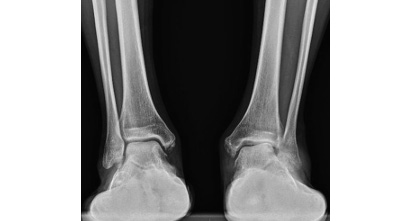

レントゲン評価では、足部を前面から、側面から、後面から評価します。

■前面から

外反型変形性足関節症の有無

詳しくは説明省きますが、stage分類に用いる為に重要です。